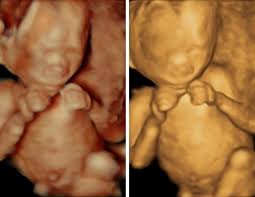

These before and after images are from actual 3d/4d ultrasound sessions performed at pregnantsee!you will enjoy the same view of your little one and even see full motion video of your unborn baby.

Baby impressions is an elective 3d 4d ultrasound imaging facility. Fetal measurements (by request) hear & see baby's heartbeat. 3d & 5d ultrasound images and 4d ultrasound video can be obtained at any stage. Baby's estimated weight and position. 30 weeks is best for 3d/4d images of what your baby will look like after it is born. Water can improve the quality of an ultrasound. At this stage, the baby has put on some weight and filled out to make features more visible, yet still enough fluid in front of baby's face to obtain great images. You'll notice that what you see varies a lot by the number of weeks of gestation. It was a very special day for my husband and i. In addition to 3d 4d ultrasound, baby bloom is known for our spectacular hd live ultrasound imaging. We do not perform medical ultrasounds. When i was 31 weeks i went back for our first 3d/4d ultrasound and it was even more special being able to see my son's face for the very first time. Book now *free rescan if face can't be seen at all.

Check out our before and after photo album on facebook and our website photo gallery for examples! Water can improve the quality of an ultrasound. Sounds like you have a very active baby! Fetal measurements (by request) hear & see baby's heartbeat. This cutting edge imaging is also known as 5d ultrasound. @cricketandhorse, i have one done at the office each week (not a 3/4d though). If you are having multiples this is also a good time to capture 3d pictures of the babies. The baby has had time to build up body fat, but still has room to move around. All digital pictures and video from your session delivered to phone or email. We are now booking in our brand new studio in downtown shawnee. Gender confirmation (by request) 5 black & white pictures. In addition to 3d 4d ultrasound, baby bloom is known for our spectacular hd live ultrasound imaging. I think they look sooo squished in there, i haven't seen any really good 3d/4d pictures past 35 weeks.